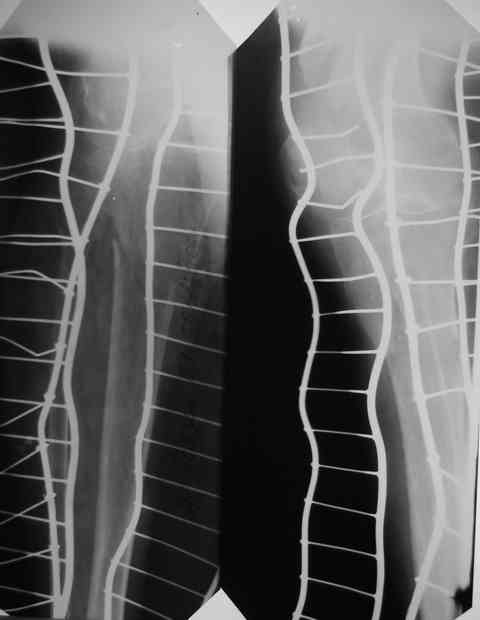

Первый перелом в июне 2002 года - перелом шейки бедра. Лечение консервативно, на данный момент имеем такую картину(см. R-gr.) Падение на бедро в июне 2006 года - не диагностирован второй косой перелом бедра на этой же стороне (просто сказали - полежать) И вот больной с переломом в/3 костей голени (опять же на этой стороне) попадает к нам в отделение. На момент поступления в н/3 бедра истинный ложный сустав. Решили первым этапом зафиксировать бедро с голенью АВФ с дистракцией на бедре (восстановить длину бедра), одновременно для жесткости пришлось зафиксировать колено. Ч/з месяц колено распустили, начали его разработку.На данный момент думаем довести голень на аппарате (или может -ЭКСПЕРТ???), а бедро после устранения всех видов смещения заштифтовать стержнем с блокированием для низких или мыщелковых переломов. НО смущает выраженный остеопороз - удержат ли запирающие винты отломки бедра!С Уважением Владимир Бахарев.

АВФ. Кстати, на этих снимках наличие ложного сустава бедра вызывает большие сомнения. Скорее можно говорить о несросшемся кососпиральном переломе бедренной кости и переломе в\3 б\берцовой кости.